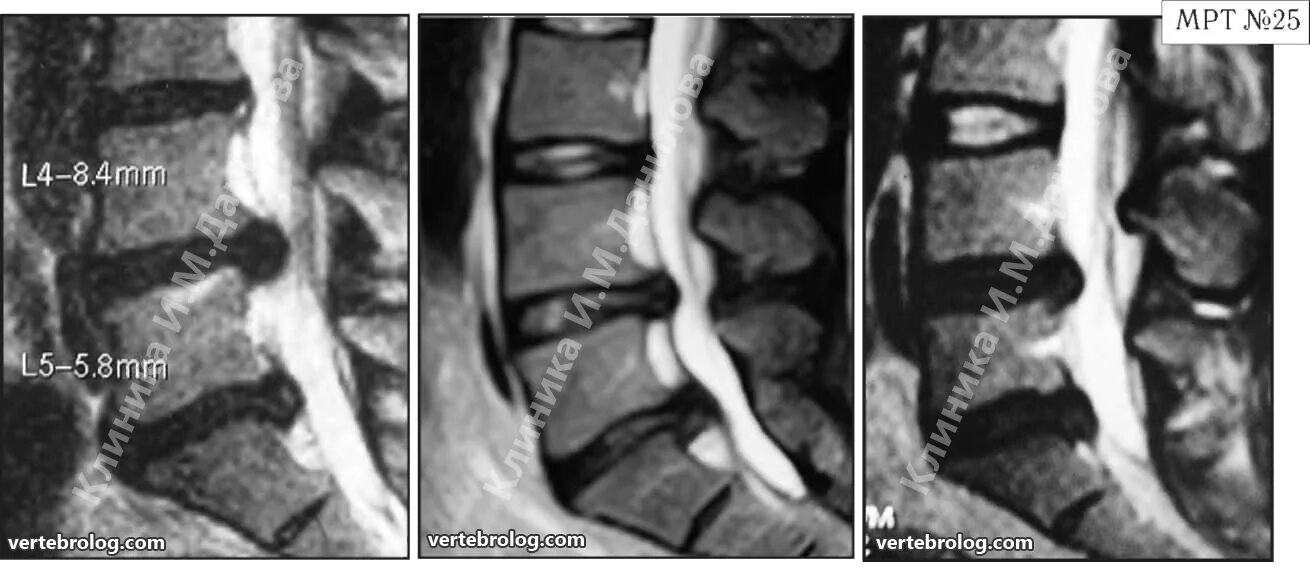

Протрузии грыжи диска шейного